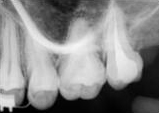

antes depois